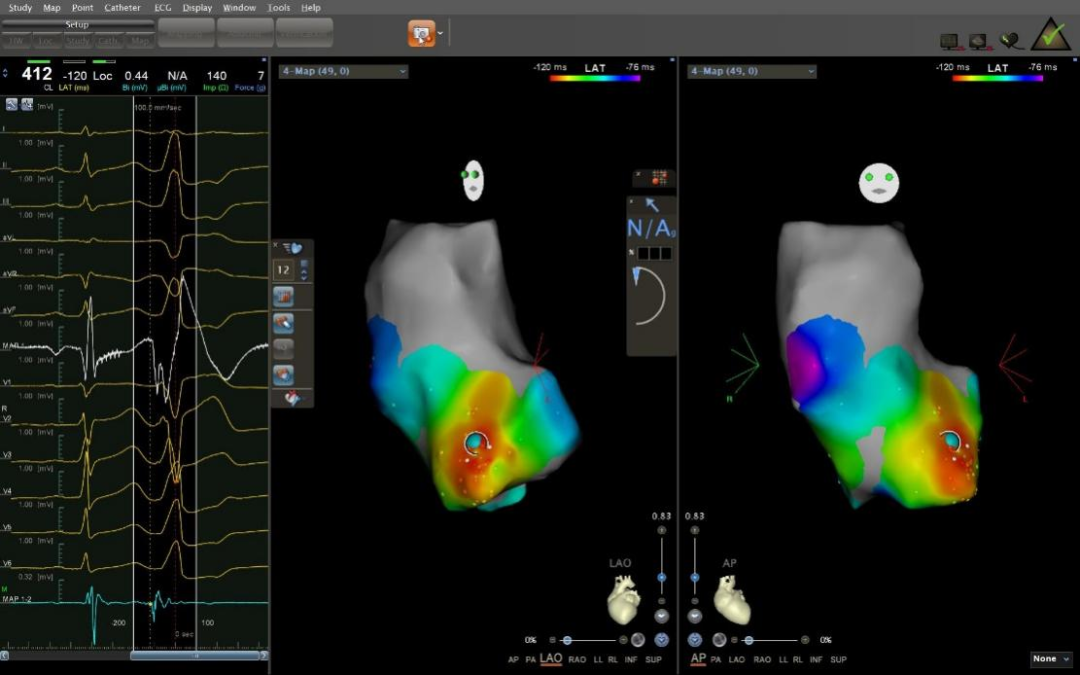

53岁男性患者,因晕厥2天于2022年5月21日入院,行动态心电图检查提示频发室早、短阵室速,来我院寻求治疗。心电图显示该型室早、室速来源于右室流出道,心内标测发现虽然右室流出道激动非常提前,但单极电图为rS型,且激动弥散,真实起源并不在右室流出道,最终在主动脉右冠窦找到最佳靶点,靶点上显示反转电位和碎裂电位,消融后室早立即消失。术后患者好转出院。

右冠窦室早消融靶点